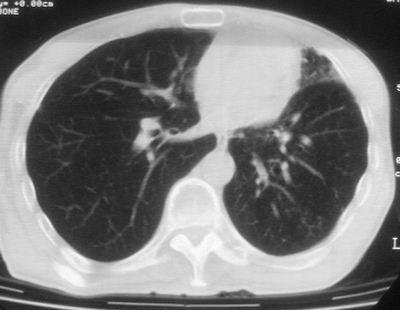

标题: CT11864:男,47岁,反复咳嗽、咯痰、咯血3年,请分析. [打印本页]

患者,男,47岁,反复咳嗽、咯痰、咯血3年,再发5天。痰培养未找到真菌、抗酸杆菌、癌细胞。

左肺上叶体积明显缩小,其内见多发透光区,纵隔向左侧移位,左肺下叶多发班片状病灶,边界模糊,1左肺上叶先天肺发育不全,2左肺下叶肺炎,

左肺上叶结核伴肺纤维化,纵隔移位,左肺下叶感染性病变,建议抗炎抗结核后复查,双肺气肿.

1.左肺上叶慢纤空2.左肺下叶炎症

考虑:左肺慢纤伴霉菌球形成、双肺全小叶型肺气肿。

1)考虑为:左肺上叶肺结核(空洞形成),伴左下肺感染;不排除霉菌感染可能。2)肺气肿。

左肺上叶结核伴肺纤维化空洞形成并左肺下叶感染,纵隔牵拉移位,建议作进一步检查排除左侧肺霉菌感染可能。